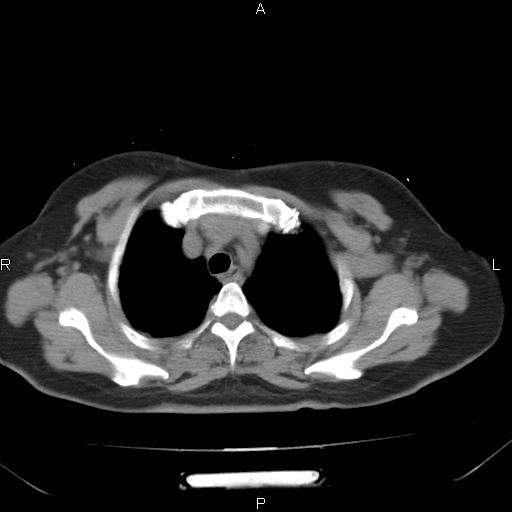

胸腺瘤

女、63Y 双眼睑下垂,早轻晚重。 胸腺瘤???

结果胸腺瘤